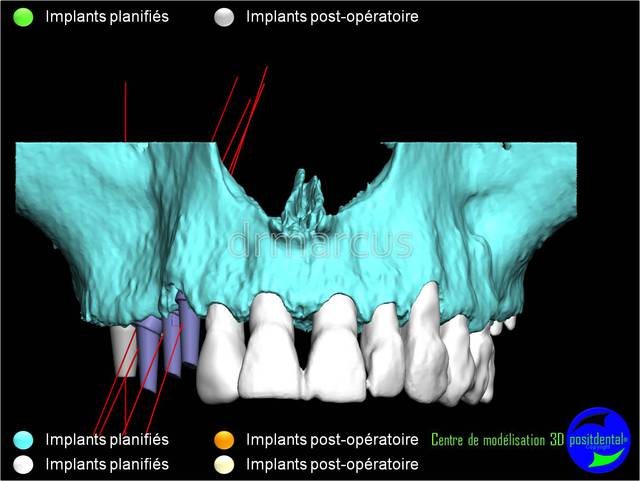

Analyse post-opératoire d’une MCI post-extractionnelle en chirurgie guidée

Cas clinique de drmarcus

Chirurgie : drmarcus

Imagerie 3D: POSITDENTAL

Dommage que ce soit scanner avant et Cone-Beam après. Il est vrai que l’interprétation peut différer. Toutefois on voit la parfaite superposition des implants entre la planification et la réalisation. J'en conclue que le système Positdental est relativement fiable ;-))))